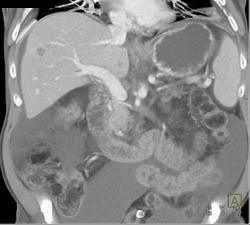

Focal Nodular Hyperplasia (FNH) Liver